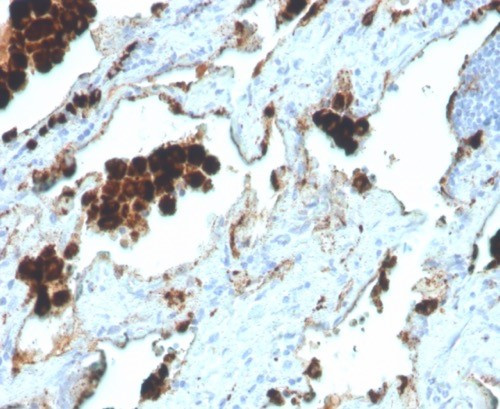

Napsin A (Lung Adenocarcinoma Marker) Antibody in Immunohistochemistry (Paraffin) (IHC (P))

图: 1 / 5

IHC analysis of Formalin-fixed, paraffin-embedded human lung adenocarcinoma. NAPSA/4400R at 2 µg/mL in PBS for 30 min RT. HIER: Tris/EDTA, pH9.0, 45 min. 2 °: HRP-polymer, 30 min. DAB, 5 min. {{ $ctrl.currentElement.advancedVerification.fullName }} 验证信息 View more